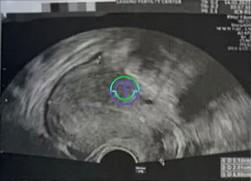

在卵巢刺激方面,颂宝医生选择了 拮抗剂方案(Antagonist Protocol),这一方案旨在防止卵泡过早排卵,帮助颂宝医生通过促排卵药物刺激卵巢,使卵子能够充分成熟,并在最佳时机取出。整个治疗周期从 月经周期第 3 天 开始。在整个过程中,医疗团队通过阴道超声检查结合定期抽血监测激素水平,精准调整了促排卵用药,并密切跟踪了 Mint 身体的每一个变化。

超声结果

右侧卵巢:卵泡大小 9, 9, 9, 8, 8, 7, 7, 6 mm → 共 8 个卵泡

左侧卵巢:卵泡大小 10, 9, 9, 9, 8, 8, 8, 8, 6, 6, 6, 6 mm → 共 12 个卵泡

LH:8.8 mIU/mL